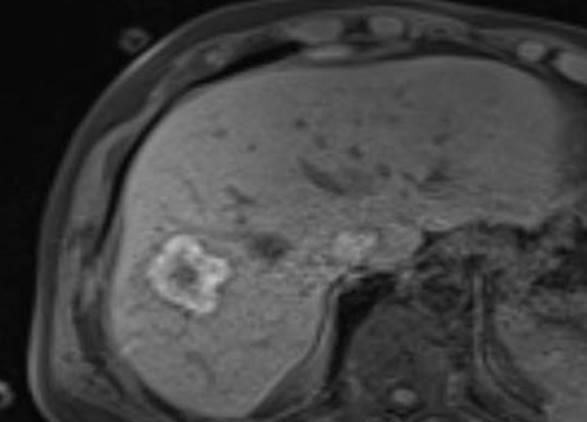

Abbildung: Bei diesem Patienten wurde ein im Röntgen nur schlecht sichtbarer Knochentumor vor der Operation unter MRT-Kontrolle mit kleinen röntgendichten Spiralen („Coils“) markiert. Damit hat der Operateur eine optimale Darstellung des Tumorbereichs bzw. der Tumorgrenzen und kann gezielter, schonender und effektiver operieren.